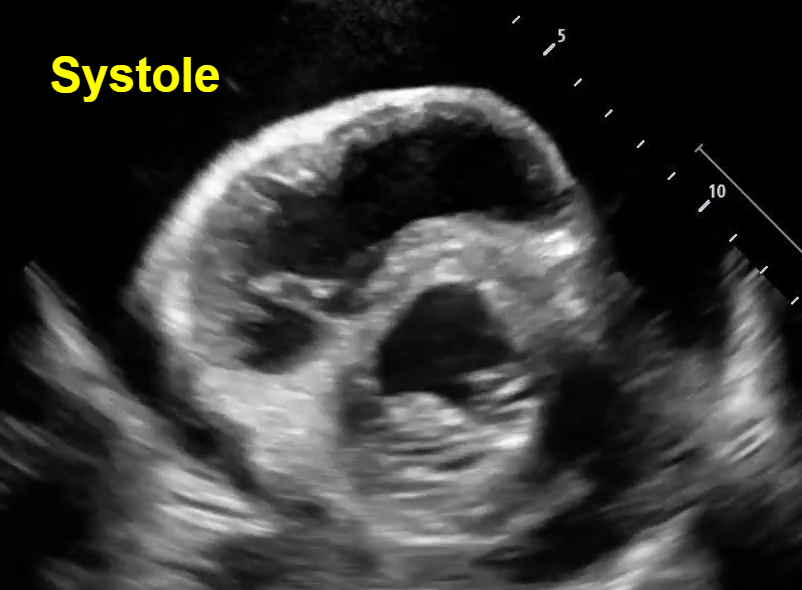

In both parasternal and short axis views seen above, there is a circumferential pericardial effusion surrounding the entire heart.

Parasternal long view: We can see the RV collapse during diastole. How do we know this is diastole? Note that we can see the opening of both the mitral valve and the tricuspid valve to allow for ventricular filling, which occurs during the diastolic phase of cardiac contraction. See clip #1 to see a video of this RV diastolic collapse.

Short axis view: Here we see an example of ‘trampoline sign’, which is the characteristic bouncing motion of the RV. In the image above, we see inversion of the RV wall during diastole (arrow). How do we know this is diastole? Again, note that we can see the opening of the mitral valve in the LV when the RV wall inverts. See clip #2 to see a video of the ‘trampoline sign’.